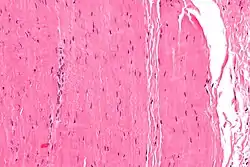

![]() عکاسی ریزنگاری of a piece of تاندون. H&E stain. | |